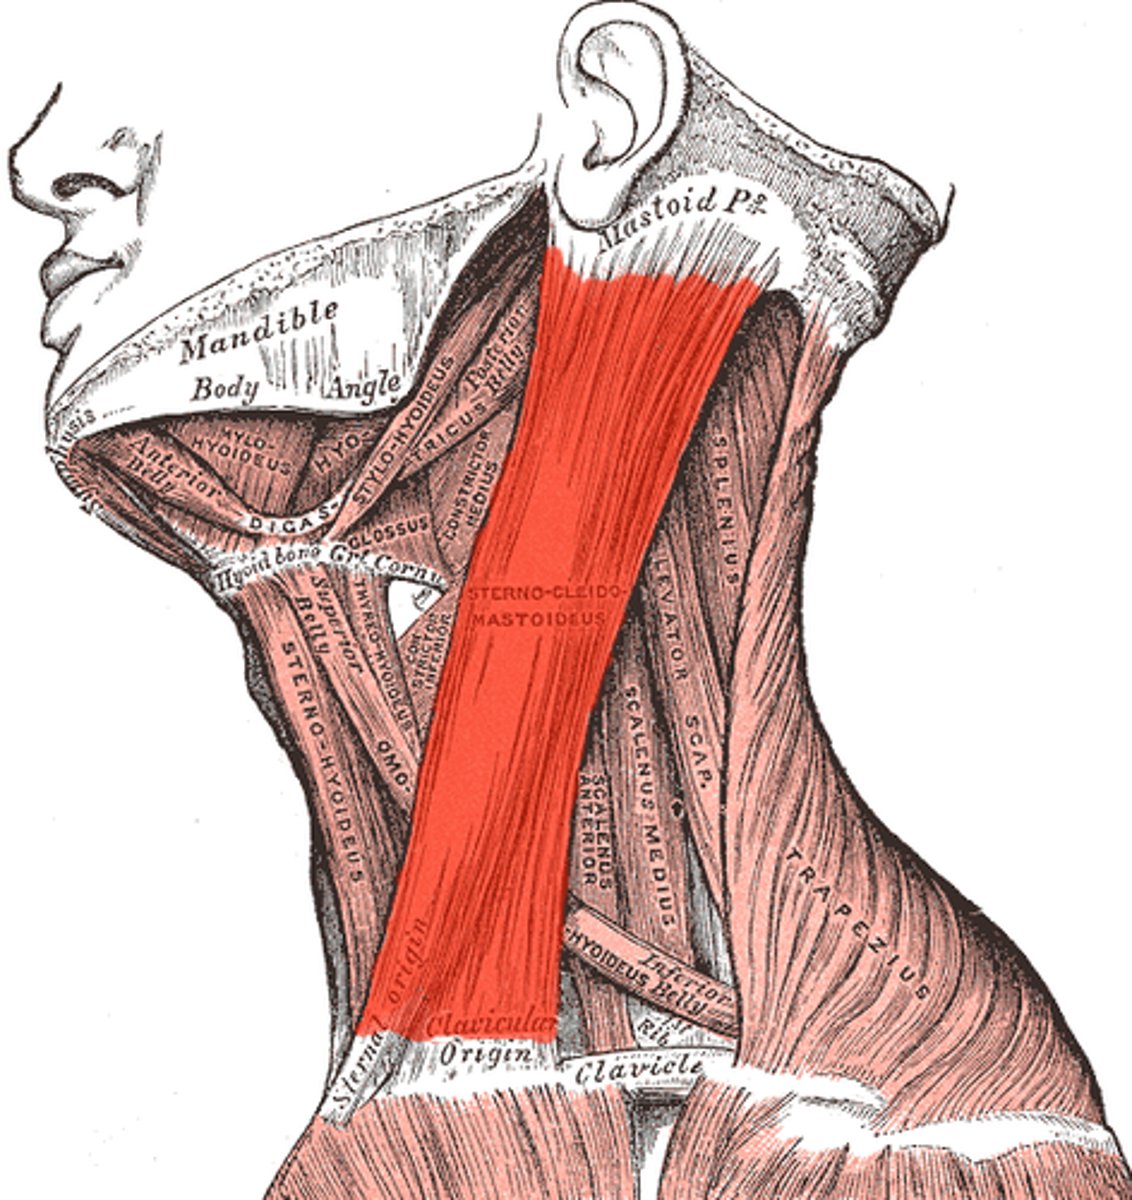

sternocleidomastoid

laterally flexes; rotates head